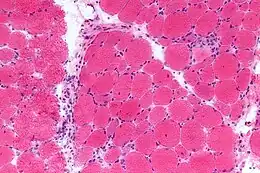

- biopsie musculaire, qui montre un infiltrat inflammatoire avec une atrophie périfasciculaire[6]. Elle peut être guidée par une imagerie par résonance magnétique musculaire permettant de visualiser un œdème musculaire[7].